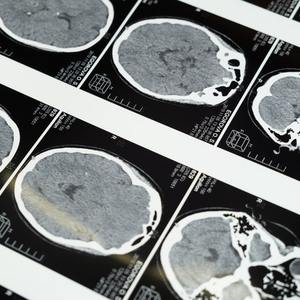

大多数重大脑疾病都源于脑功能网络的病变,但普遍缺乏有效治疗手段,关键原因在于对人类脑功能网络和疾病相关神经环路的检测非常困难,严重阻碍了对脑疾病机制的理解。迄今为止,在人类生命体的研究中获诺贝尔奖最多的是脑科学,但大脑这个由上千亿神经细胞组成的器官与人体的关联至今还未被完全参透。

由于对病源和疾病发展学方面知识不足,许多大脑疾病目前仍属不治之症。通过深入了解大脑相关机制和作用过程,科学家正试图将这些发现转换成治疗人类生理和心理病痛手段上的突破。这其中主要包含精神类疾病和脑部退化性疾病。

包括抑郁症、情绪问题、长期疼痛、精神分裂等在内的精神力疾病对认知和情感能力造成损害,并且会严重影响患者应对生活的能力。脑部退化性疾病则包含了老年痴呆症、帕金森综合症、震颤性麻痹和运动神经元疾病等对病患身体活动能力伤害巨大的疾病。